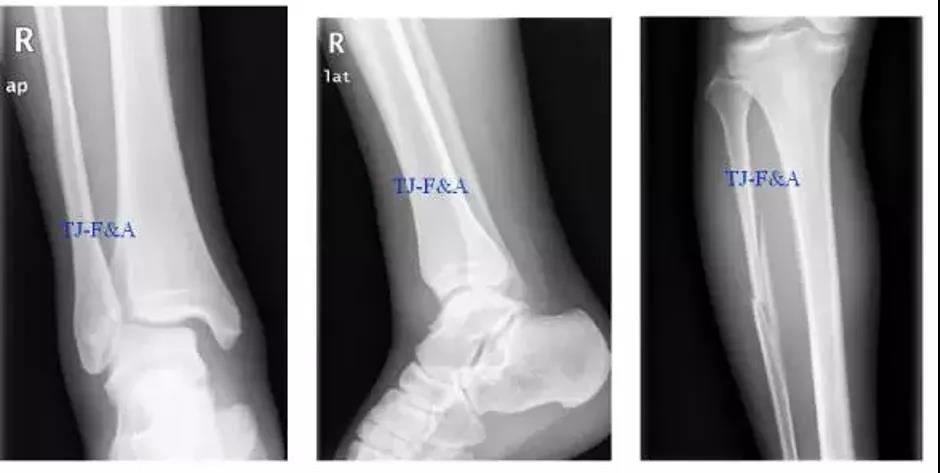

术前

术前DR